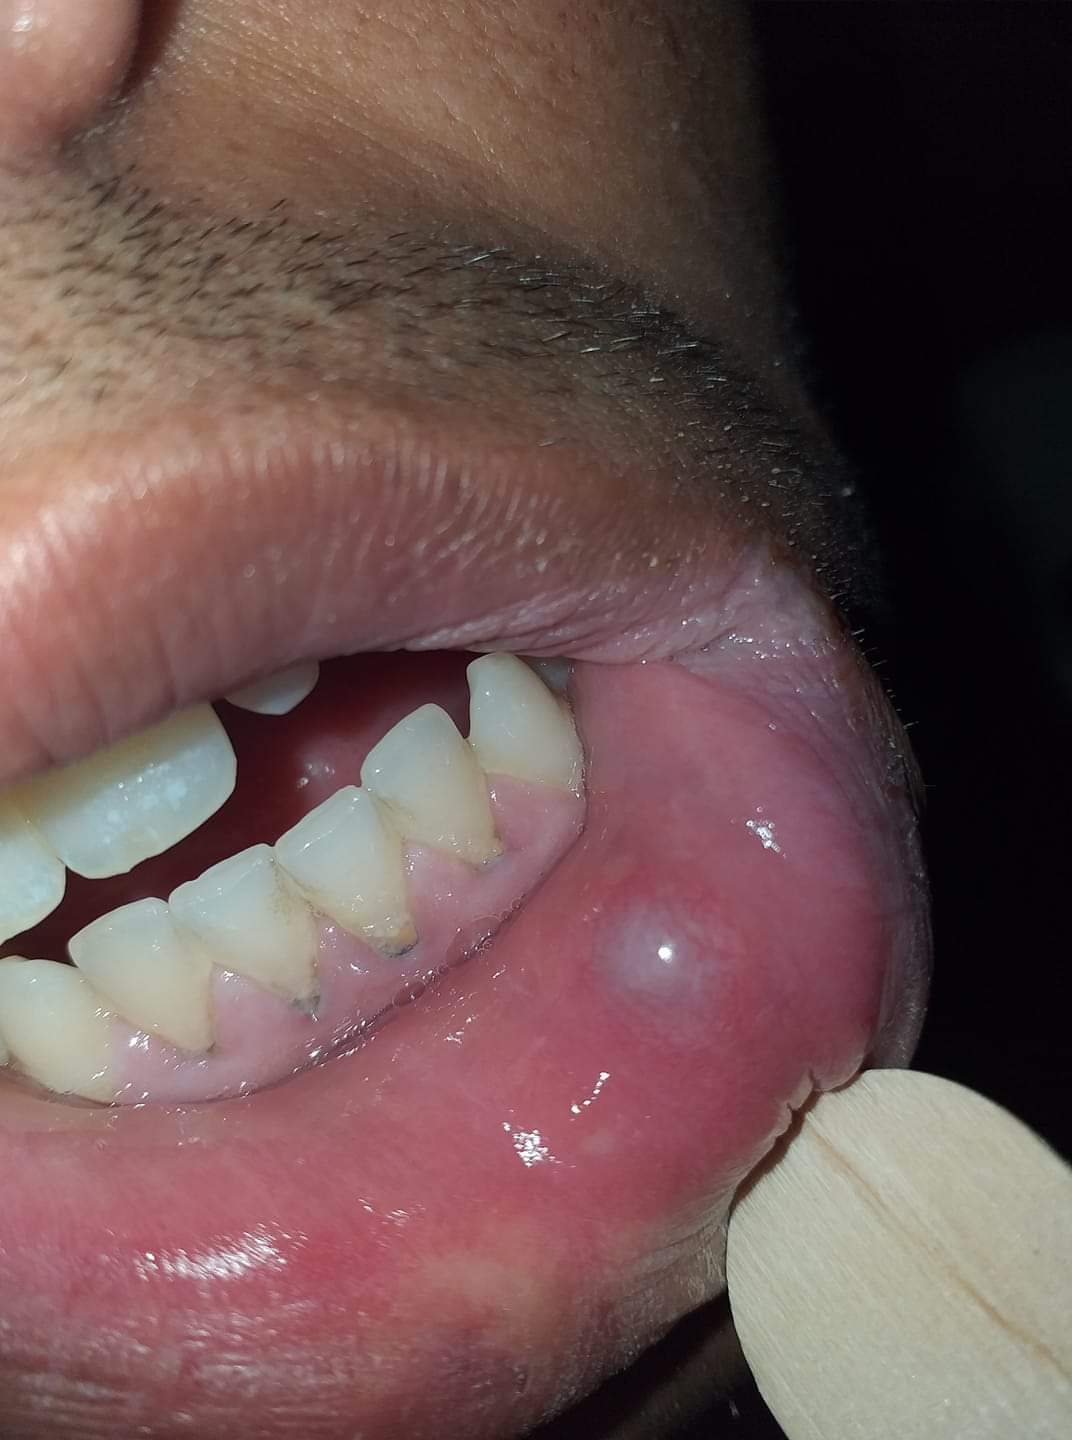

Bonjour Dr que pensez vous de cette masse indolore de consistance molle qui depuis 2 mois ....diagnostiqué probable svp.....+ la prise en charge

Allez parce je suis bloqué sur mes chiottes , j’ai le temps de répondre au comique : mucocèle

Kyste muccoïde

À surveiller parfois ils disparaissent tous seuls.

Sinon exérèse